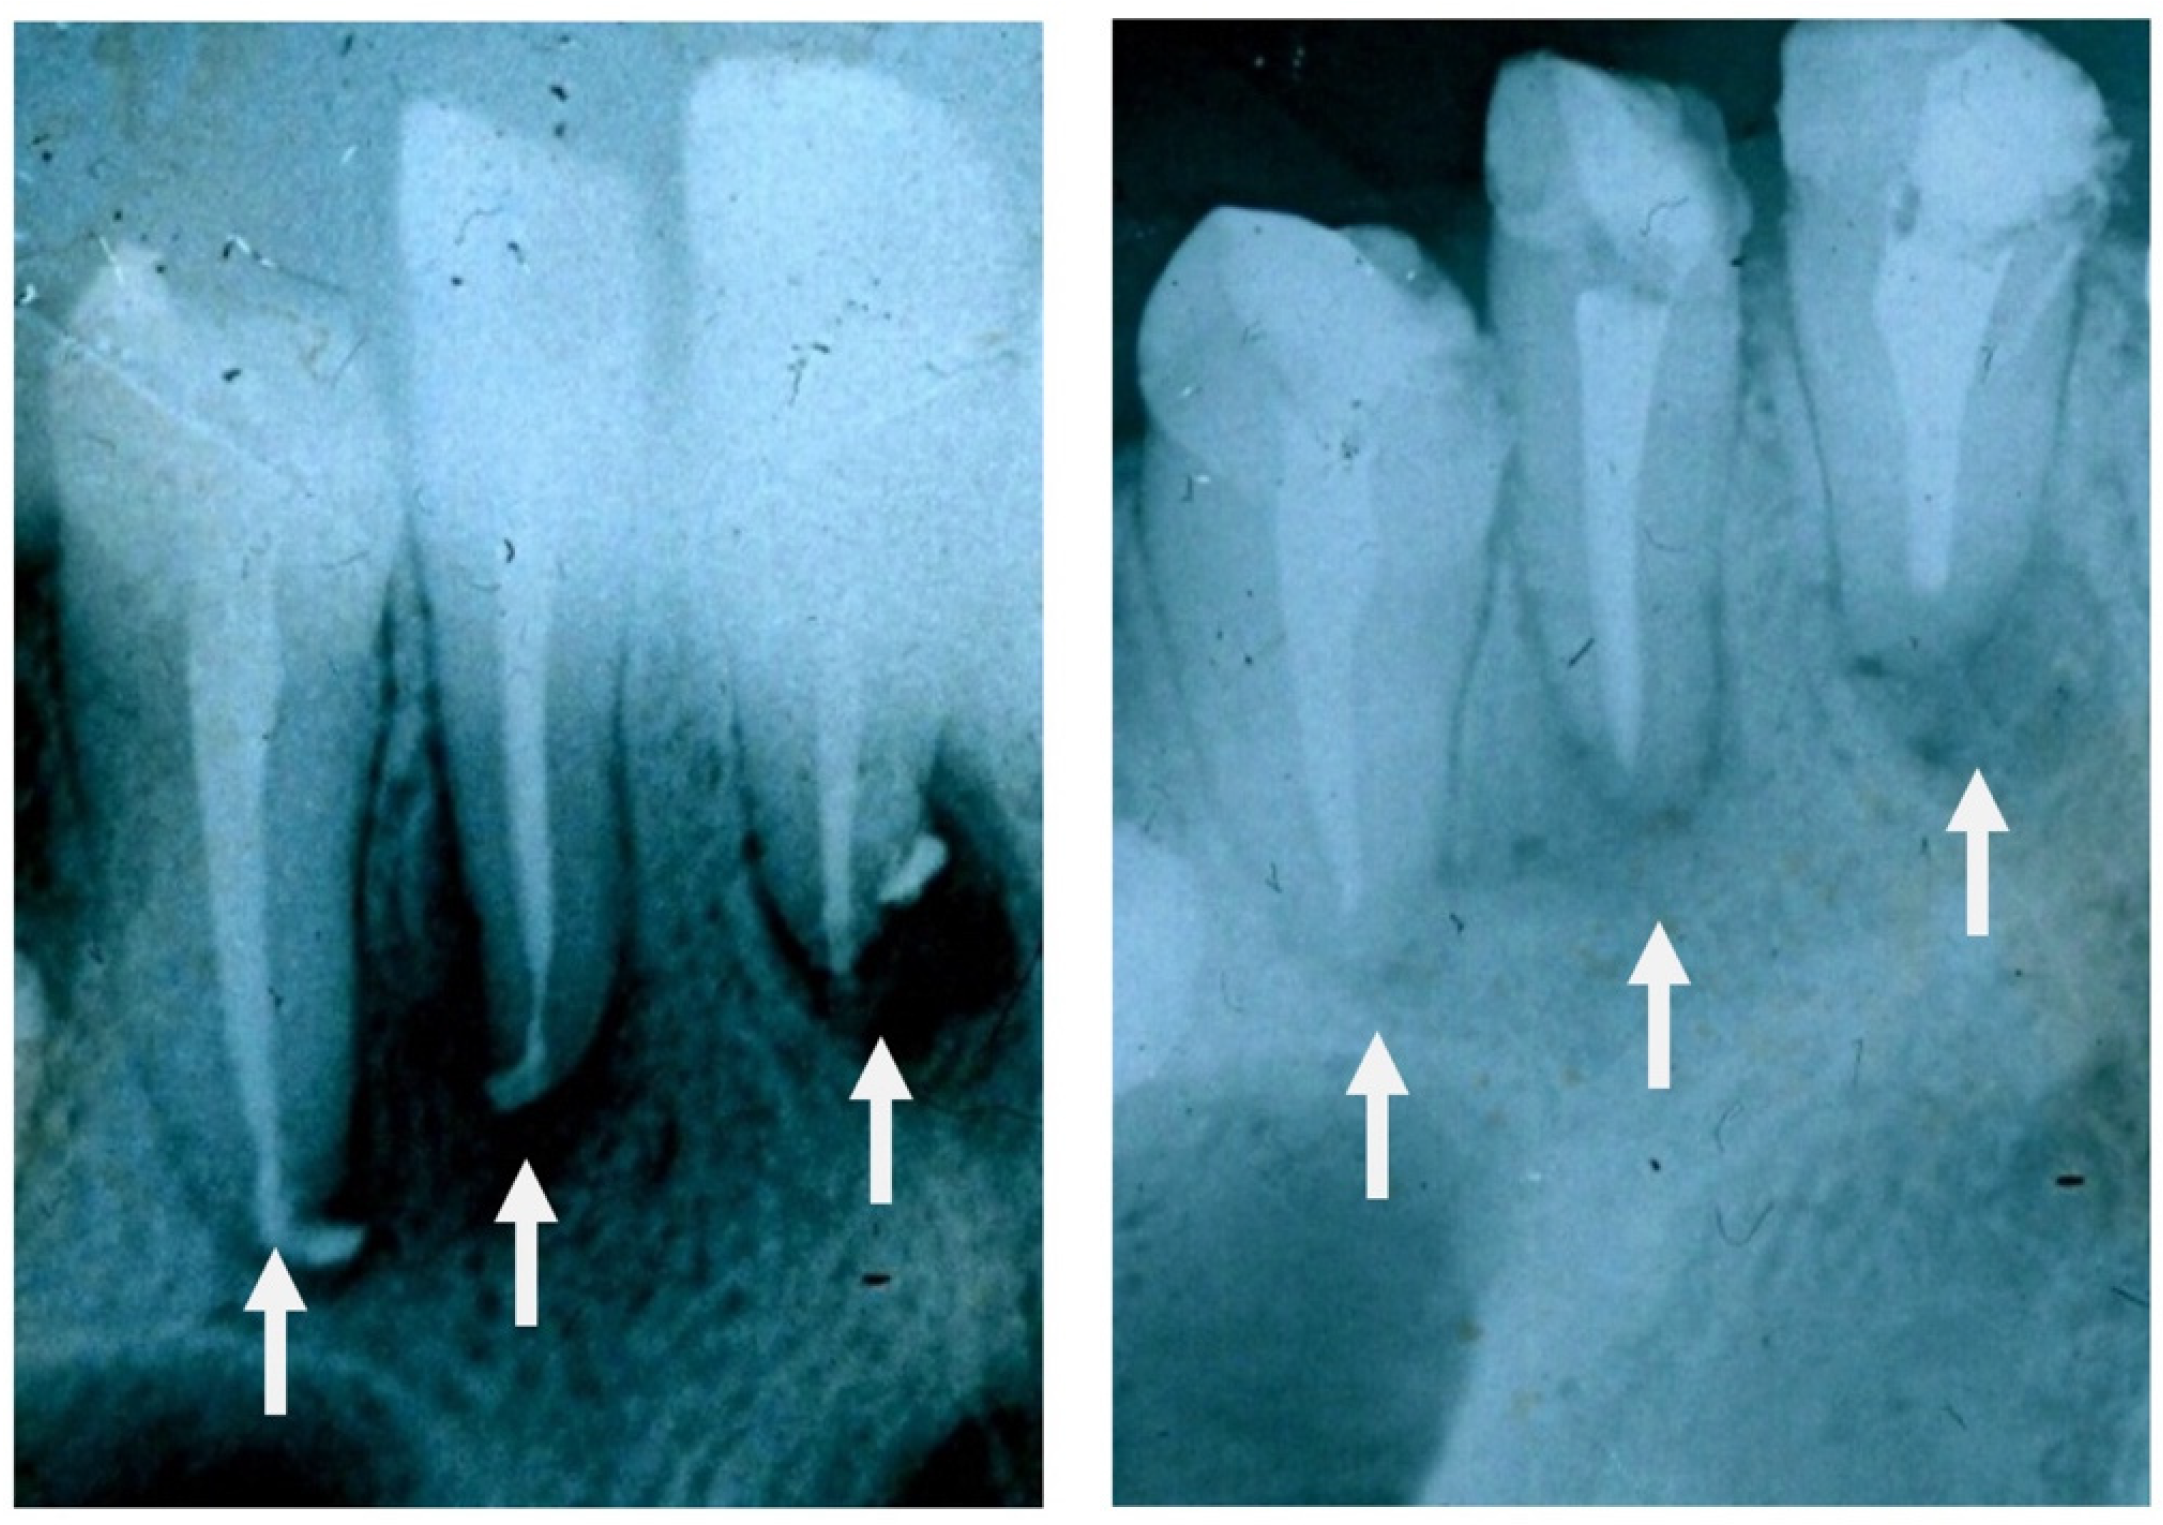

6. In Vivo Experiments and Clinical Trials

7.1. GC Dental Implants